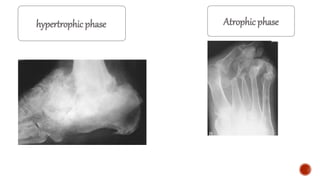

hypertrophic phase Atrophic phase

LICKED CANDY STICK

WEIGHT BEARING JOINTS NON WEIGHT BEARING JOINTS